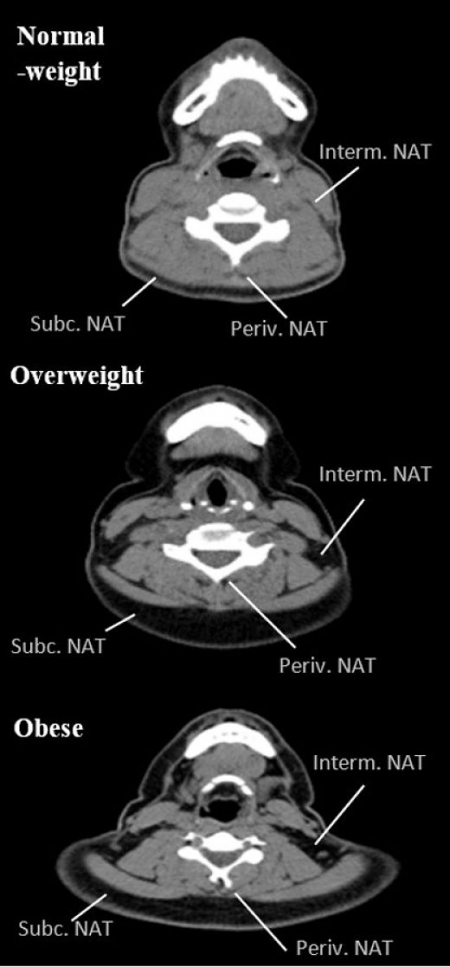

Tener mucha grasa en el cuello aumenta las posibilidades de sufrir problemas de corazón, según un estudio

Investigadores de la Universidad de Granada señalan que la acumulación de grasa en el cuello es un factor predictor de adiposidad central y total, riesgo cardiometabólico y perfil inflamatorio en adultos jóvenes sedentarios